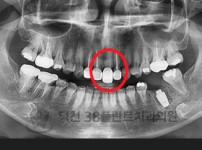

치료전후